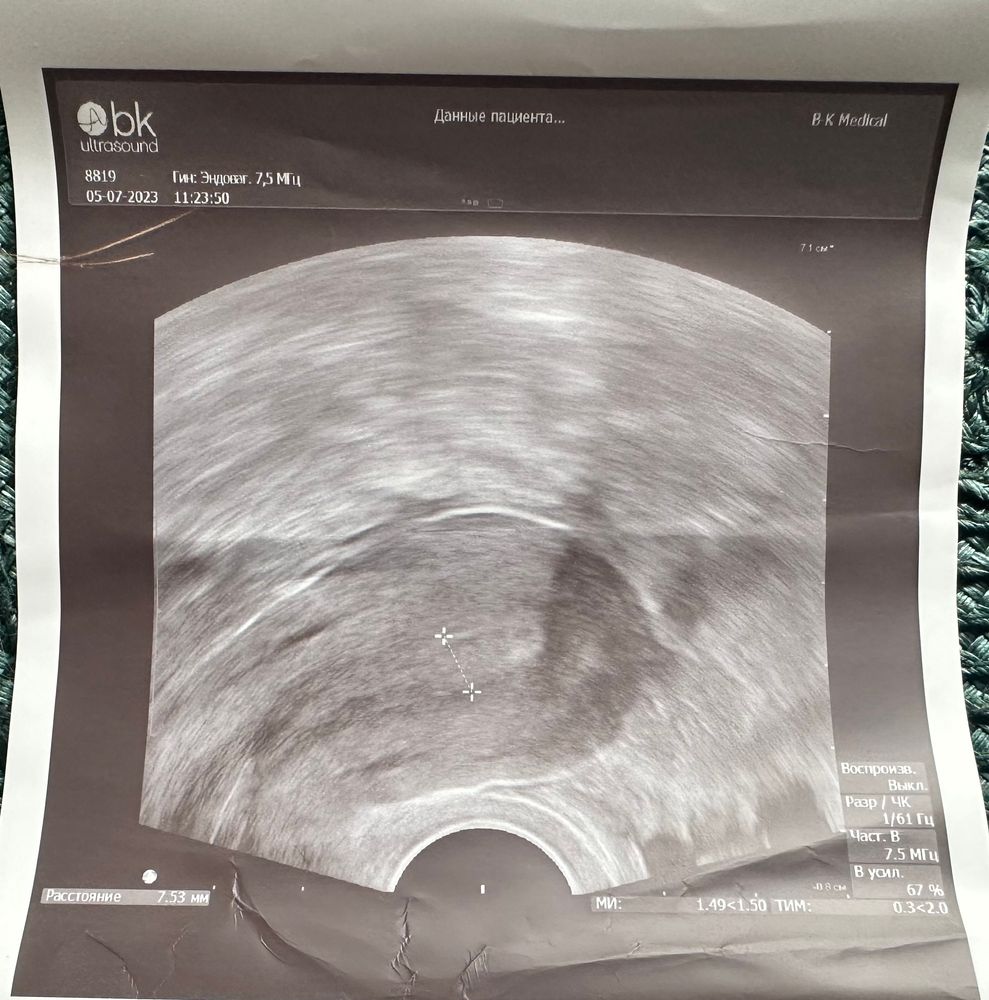

девушки,сегодня 13 дц в крио,была на узи,сказала эндометрий не очень по мм,но красивый.

Сказала три разных толщины,прямо и растянуть если сильно.

итог: 5,59 мм; 7,53мм; 6,86мм

Так вот какой верный то?Как понимать если надежда,что дорастет до 8мм хотя бы?Я так и не поняла.

фото прикрепляю,все за один сеанс